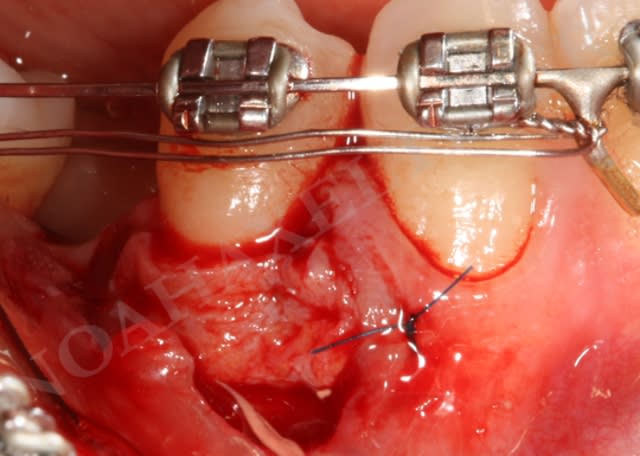

Lit receveur loll9i - Eugenol

Lit receveur bf5bsr - Eugenol